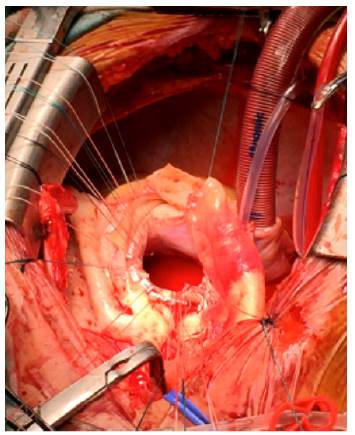

Exposure of the aortic ring with appropriate fixation points for subsequent placement of prosthetic

Fig 4: Exposure of the aortic ring with appropriate fixation points for subsequent placement of prosthetic

Exposure of the aortic ring with the appropriate fixation points after prosthesis placement. Fig 5b. Replacement of the aortic root using composite prosthesis and Bentall coronary reconstruction. a: extracorporeal circulation system. b: aortic ring with corresponding fixation points. c: prosthetic material.

Fig 5A: Exposure of the aortic ring with the appropriate fixation points after prosthesis placement. Fig 5b. Replacement of the aortic root using composite prosthesis and Bentall coronary reconstruction. a: extracorporeal circulation system. b: aortic ring with corresponding fixation points. c: prosthetic material.